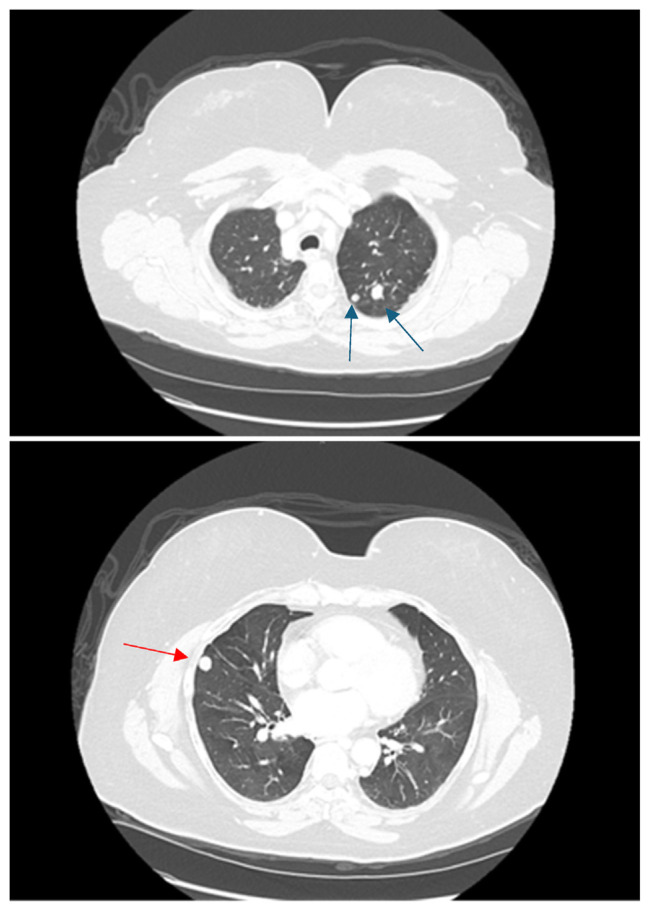

Pheochromocytomas and paragangliomas (PPGLs) are rare neuroendocrine tumors arising from adrenal medulla and extra-adrenal paraganglia. Metastatic pheochromocytomas, pose diagnostic and therapeutic challenges due to their atypical presentations and potential for malignant transformation years after primary tumor resection. We report a case of 61-year-old woman who presented with intermittent cough, shortness of breath, and elevated blood pressure 6 years after resection of primary adrenal pheochromocytoma. Imaging revealed bilateral pulmonary nodules, a retroperitoneal mass, and L4 vertebral involvement, raising suspicion for metastatic pheochromocytoma. Elevated serum meta-nephrines and normetanephrines, alongside tissue biopsy and MIBG imaging, confirmed diagnosis. Germline genetic testing did not reveal any pathogenic mutations. The patient underwent CT-guided cryoablation for retroperitoneal lymph nodes and scheduled for radiofrequency ablation (RFA) of metastatic lesions. This case underscores evolving understanding of PPGLs, challenging "10 % rule" regarding metastasis and inheritance. While mutations in genes such as SDHB are associated with increased metastatic risk, sporadic cases like this highlight need for lifelong surveillance in all patients' post-resection of primary tumor. Ablative techniques, EBRT, and emerging systemic therapies are promising methods for managing metastatic disease. This case highlights importance of long-term follow-up and genetic testing in patients with PPGLs, even in absence of hereditary mutations, to detect and manage late-onset metastatic disease efficiently.